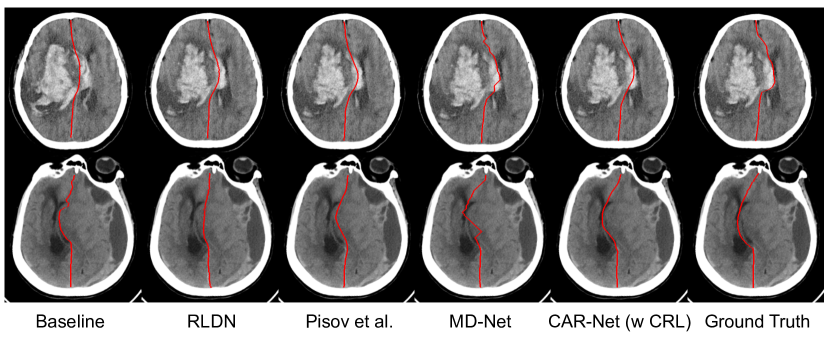

We provide qualitative and quantitative comparisons to three state-of-the-art algorithms of brain midline delineation: RLDN [11], Pisov et al. [8] and MD-Net [10] on our inhouse dataset and the CQ dataset. All the experiments take the aligned image IAsubscript𝐼𝐴I_{A} as input for fair comparison. As shown in Table. 2, our proposed model performs better than all the three methods in four evaluation metrics on both datasets, only except the comparable ASD on the inhouse dataset with the MD-Net. The experiment shows the good generalization capability and promising effectiveness of our proposed method. Fig. 4 shows some delineation results of the challenging deformed brain midline. It can be inferred that our proposed method can delineate a more accurate and smoother midline, compared to the other methods, which can provide more accurate clinical judgement of pathological deformation of brain. Furthermore, the parameters of our proposed model are 3.90M, fewer than the ones of the other three methods, which can meet the needs of practical application better.

Refer to caption

Figure 4: Qualitative comparison between baseline, RLDN, Pisov et al., MD-Net and CAR-Net with CRL, showing two examples of the midline delineation.